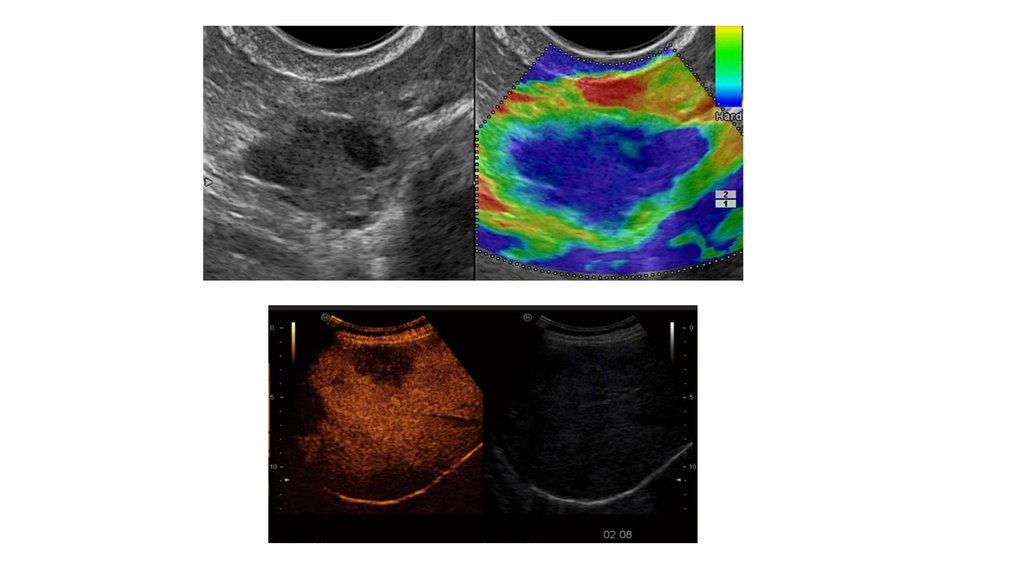

13. Мультимодальная визуализация

Мультимодальная визуализация УЗИ — технология сравнения

ультразвуковых изображений в режиме реального времени с

изображениями, полученными различными методами лучевой

диагностики (КТ, МРТ) на одном экране.